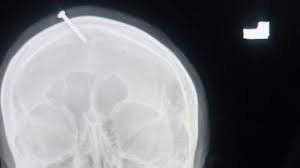

Jeshi la Polisi nchini Pakistan linamtafuta Mganga wa Kienyeji anayedaiwa kugongelea Msumari wa wa sentimita tano kwenye kichwa cha Mwanamke Mjamzito kwa Imani atajifungua Mtoto wa Kiume.

Vyanzo vya habari nchini humo vimeripoti kuwa Mwanamke huyo mwenye ujauzito wa umri wa miezi mitatu alifika katika hospitali moja katika jiji la Peshawar akiwa amepigiliwa msumari wa sentimita 5 kichwani mwake na inadaiwa aliwafahamisha madaktari kwamba alitekeleza kitendo hicho yeye mwenyewe.

Daktari wa magonjwa ya mfumo wa neva Haider Suleman, ambaye alimtibu mwathiriwa katika Hospitali ya Lady Reading ingawa msumari ulikuwa umepenya kwenye fuvu la kichwa cha mwanamke huyo, haujafika kwenye ubongo wake.

Dk Haider Suleman, daktari bingwa wa upasuaji wa neva, aliiambia Dawn, kwamba msumari ulikuwa umepenya ndani kabisa ya fuvu la kichwa cha mwanamke huyo na familia ilifanya majaribio ya kuutoa msumari huo nyumbani lakini ikashindikana.